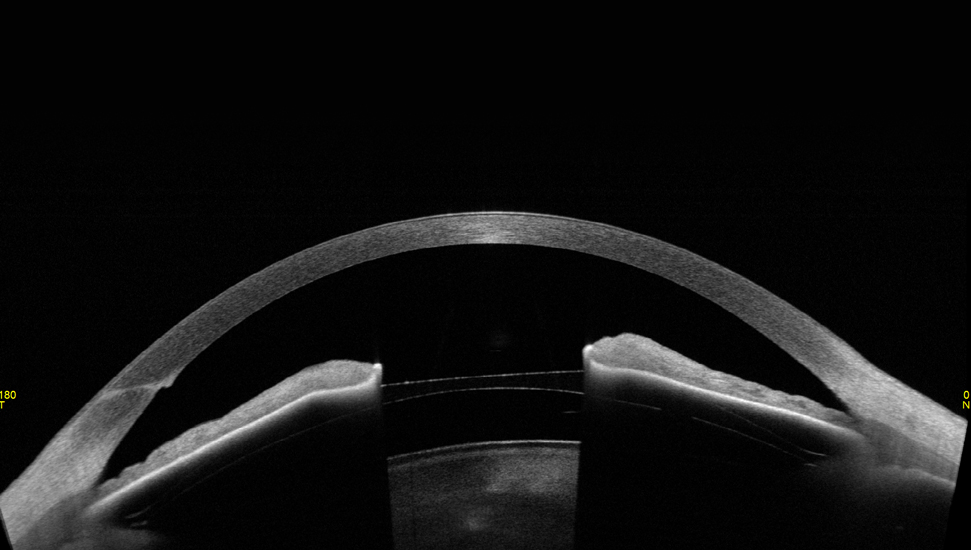

W aplikacji STAR 360°, CASIA2, dzięki automatycznemu wykrywaniu ostrogi twardówki mierzy kąt przesaczania na pełnym obwodzie przedniego segmentu, co zapewnia szczegółowe parametry umożliwiające perfekcyjną diagnostykę jaskry.